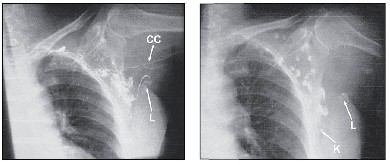

Při přímé lymfografii HK se na těchto snímcích zobrazují jako první přívodné lymfatické kolektory, následně se zobrazují laterálně uložené uzliny v axile, poté uzliny v centrální části axily a následně uzliny přilehlé k hrudní stěně a uzliny ve vrcholu axily.

Na lymfografiích se ukázalo, že z HK odvádějí lymfu 2-4 hlavní přívodné kolektory, které v 5 případech z 9 vstupovaly do jedné uzliny, která byla umístěná v laterální části centrální axily (v úrovní 4.-6. žebra). Tato uzlina imponovala jako sentinelová uzlina pro HK. Ve 4 případech se kraniálně zobrazil kolektor, který směřoval přímo do uzlin v horní části centrální axily. Tento „kraniální“ kolektor měl četné anastomozy s ostatními kolektory ještě před vstupem do axilárních uzlin. Jako nejdůležitější nález však hodnotíme zobrazení četných lymfatických anastomoz, které probíhají mezi všemi zobrazenými uzlinami v axile, včetně kaudálně uložených uzlin v oblasti 4.-6. žebra, tedy tam, kde můžeme předpokládat nejčastější lokalizaci sentinelové uzliny prsu.

Na snímcích po 24 hodinách od aplikace se již nezobrazují lymfatické kolektory (v důsledku jejich vyprázdnění), ale zobrazuje se množství uzlin, které jsou rozptýlené ve velkém prostoru. To nasvědčuje tomu, že kontrast se z horní končetiny následně téměř rovnoměrně rozptýlil do nečekaně velkého množství lymfatických uzlin. Při topografickém srovnání se zobrazenými skeletárními strukturami (žebra, lopatka, pažní kost) můžeme usuzovat, že jsou zobrazeny pravděpodobně všechny skupiny spádových lymfatických uzlin, včetně uzlin běžně nepřístupných chirurgické intervenci (supraklavikulární). Vzhledem k jejich počtu a lokalizaci blízko u hrudní stěhy (žeber) lze předpokládat, že se současně jedná o spádové lymfatické uzliny pro prs. Kontrastní látka tedy neproudí lymfatickým řečištěm pouze centrálním směrem, ale v oblasti axily dochází k jejímu disperznímu rozptýlení do velkého množství spádových uzlin.

Příklady lymfografií